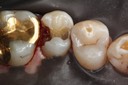

Photos of Clinical Operations

Drs. Peter Kearney, Terry McKay, John St. Germain, and Laurie Vanzella - Mentors